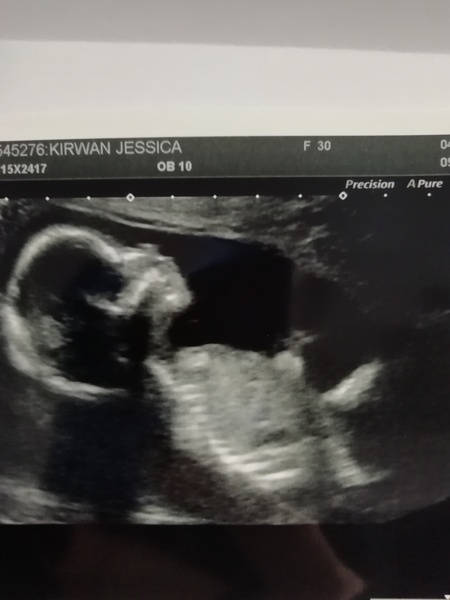

Jesskir89 · 04/10/2019 08:07

@keyboard91 sounds like you're struggling. Try and take it easy. I'm getting ready for my 16 week reassurance scan due to prior missed mc I'm nervous as hell!

Jesskir89 · 04/10/2019 09:55

Scan went well ladies :)

Lovely scan @Jesskir89 😍

@Jesskir89 Ah look Smile how lovely and exciting.

Ah @Jesskir89 that’s fab I know you were anxious.

Lovely scan @Jesskir89

@sep30 @misspepper8 @blondie87 and @munchymunchkin thank you :) I'm relieved now. @misspepper8 hope you're better soon. @whiskersonkittenss if it begins with a c I would say Brooks campbell

Lovely scan @Jesskir89 🥰